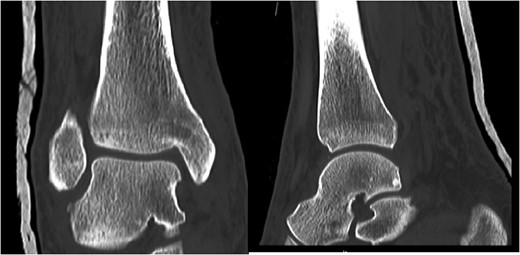

A 30-year-old male patient presented to Emergency Department (ED) following a run over injury. The patient described the mechanism of injury as moving his body over his run over foot. On clinical examination, there was obvious deformity and swelling of the right ankle. Dorsalis pedis pulse was felt but weak compared to the contralateral side with a capillary refill time under 3 s. The posterior tibial artery could not be palpated because of the deformity. X-rays showed posterior ankle dislocation without associated fractures (Fig. 1). Urgent reduction of the dislocation was done under sedation in ED. The knee was first flexed to relax the tendon Achilles then longitudinal traction with gentle forward force applied to the heel with immediate reduction of the deformity achieved. The foot was reassessed for vascular status. Triphasic pulse in both drosalis pedis and posterior tibial artery was detected with hand held Doppler. Ankle was immobilized in posterior below knee back slab to accommodate for swelling and check x-rays confirmed reduction of the ankle joint (Fig. 2). CT scan was done afterwards to define any subtle incongruity or osteochondral fragments entrapped in the joint. CT did not show any associated fractures and showed congruent reduction of the ankle joint (Fig. 3). Patient was mobilized touch weight bearing for first 2 weeks. The back slab was changed for weight bearing short leg cast and progressive weight bearing was allowed for the following 4 weeks. At 6 weeks follow up, plaster was removed and on examination patient still had moderate tenderness over the medial joint line and deltoid ligament area. Also, patient had limited range of plantar and dorsal flexion. Referral for physiotherapy was done for start of functional rehabilitation and range of motion exercises and in mean time MRI was done to delineate extent of ligamentous injury. MRI showed bone bruising of the lateral malleolus, medial malleolus and lateral talus (Fig. 4). The anterior talufibular ligament (ATFL), calcaneofibular ligament (CFL), posterior talofibular ligament (PTFL) and deltoid ligaments were sprained but intact. At 12 weeks follow up, patient could walk normally without any symptoms of instability and achieved 20° of both plantar and dorsal flexion. At 16 weeks, patient achieved full range of motion of ankle and was able to return to work. At 24 weeks follow up patient was able to resume his sport activates as preinjury level.

Post reduction films showing adequate reduction of the ankle joint with no talar shift or syndesmotic injury.